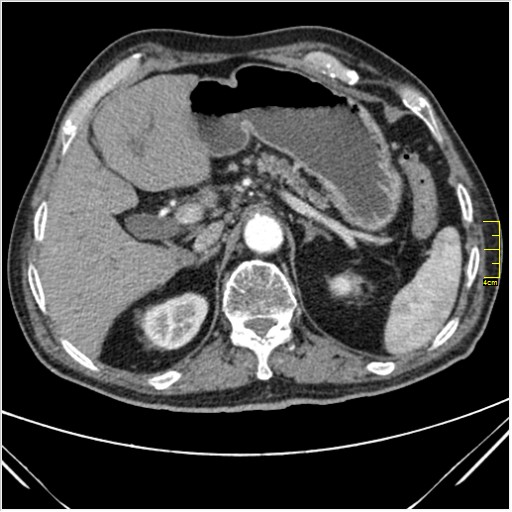

Мужчина 62 года с желтухой

Опухоль головки поджелудочной железы, расширение холедоха и панкреат. протока (Double Channel sign)

Карциномы панкреас гиподенсны на КТ с болюсом, т.к. содержать много соединительной и фиброзной ткани, в отличие от нормальной ткани железы, которая (как любая железа) хорошо васкуляризирована. Поэтому если видим в панкреас солидное гиподенсное образование - всегда настораживает на предмет рака. Второй момент: обязательная оценка взаимоотношения опухоли к ВБА и ВБВ, на предмет оценки операбельности.